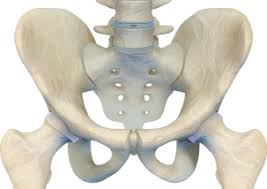

고관절 통증이 자주 나타나는 위치

• 사타구니가 깊게 아픔 : “관절 안쪽” 느낌이 강하면 고관절 자체 문제(관절염, 충돌증후군, labrum 등) 가능성을 생각합니다.

• 엉덩이/뒤쪽 통증 : 허리(요추) 문제와 구분이 필요할 수 있어요.

• 허벅지 바깥쪽(골반 옆 ‘뼈 튀어나온 곳’)이 아픔 : 옆으로 누우면 더 아프고, 눌렀을 때 통증이 심하면 점액낭염(대전자 점액낭염) 쪽이 흔합니다.